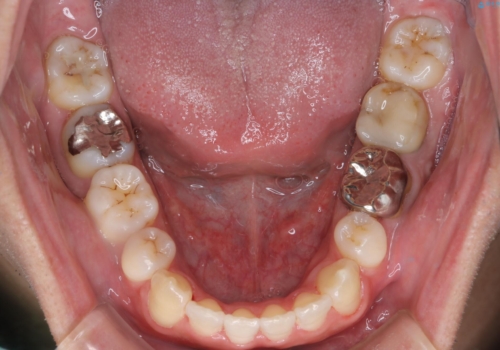

若干の口元の突出感もあったため、抜歯によるスペースを利用し、がたつきの改善と前歯の後退をを行いました。

見た目、嚙み合わせ及び、治療期間や施術内容にご満足いただきました。